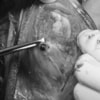

関節鏡検査を実施いたしました。関節鏡検査では、重度の滑膜炎および前十字靭帯の完全断裂が認められました。半月板に損傷は認められませんでした。

断裂前十字靭帯の除去を行いました。その後 TTA(Tibial tuberosity advancement)を実施しました。

写真の膝関節の垂直線を綿棒の木柄が表しており、遠位の脛骨粗面との位置関係が平行ではありません。